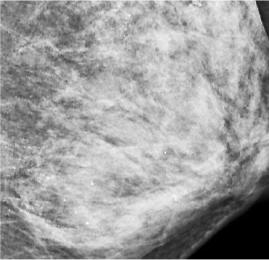

武汉48岁的朱女士未婚未育,体检时发现右侧乳房有包块。

医生在对她的左侧乳房进行乳腺X线检查时,发现里面全部都是细小如沙子一样的钙化灶,布满整个乳腺。

原来,朱女士一向注重保养,这些年一直在外面做精油推拿按摩,保养胸部。

医生分析,极有可能是按摩师用力不当损伤了腺叶乳管,导致乳腺出现坏死性细小点状钙化。

悲剧的是,朱女士最终被确诊为乳腺浸润性癌,接受了全乳切除和淋巴结清扫手术。